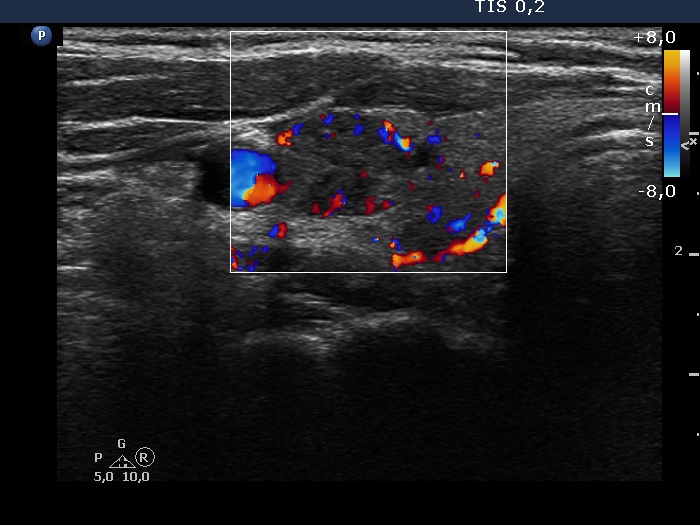

Ultrasonography. The thyroid was echonormal. Beside several hypoechoic and cystic lesions without any clinical significance, both lobes had a hypoechoic nodule. The presentation of them was very similar, both had echogenic granules and showed peripheral vascularity. However, the echogenic figures in the right nodule were probably back wall figures while those in the left nodule were microcalcifications. Regarding the vascularity, the left nodule showed perinodular blood flow while the right did not.